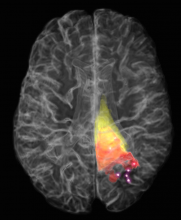

2017 Québec Science Discovery of the Year Award goes to the cancer-detection probe developed by Kevin Petrecca and Frédéric Leblond! - Photos